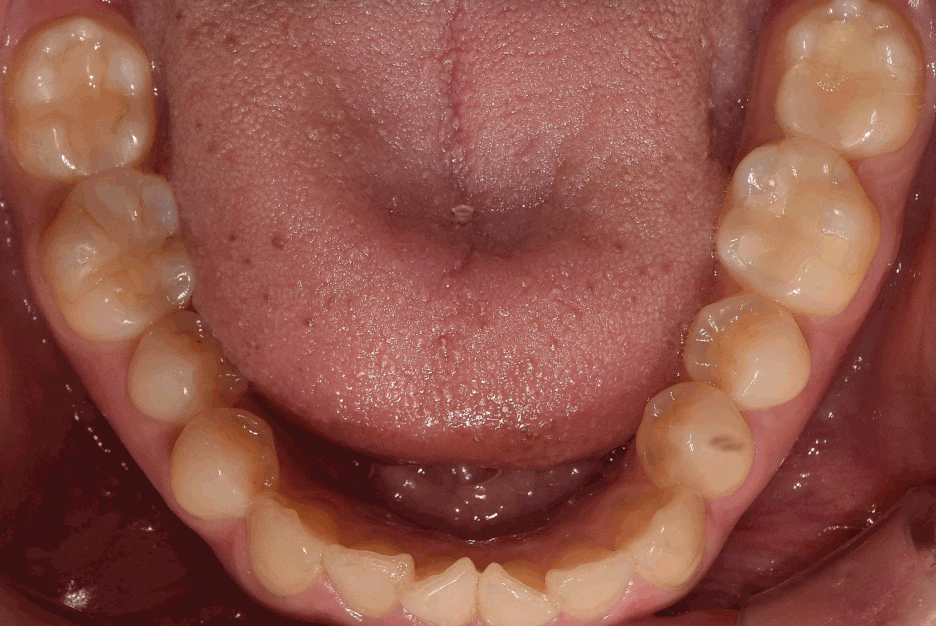

구강 내 사진을 먼저 보여드리면, 윗니가

아랫니를 깊게 물고 있어서 아랫니가 거의

눈에 띄지 않는 것을 보실 수 있습니다.

딱, 전형적 과개교합 의 양상을 보여주고 있습니다.

그러면서 치아의 중심선이 맞지 않으면서

악궁의 크기 또한 비대칭인것을 볼 수 있네요.